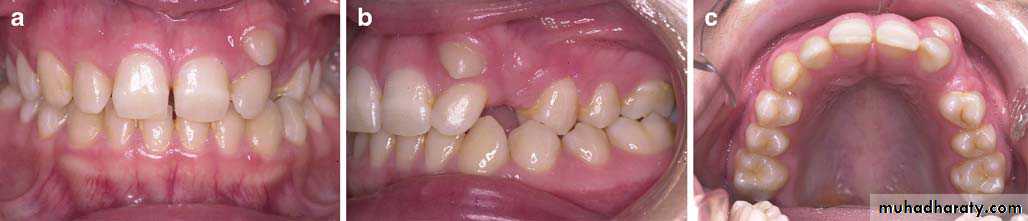

Position of canine root apex anteroposteriorly

Vertical canine crown height